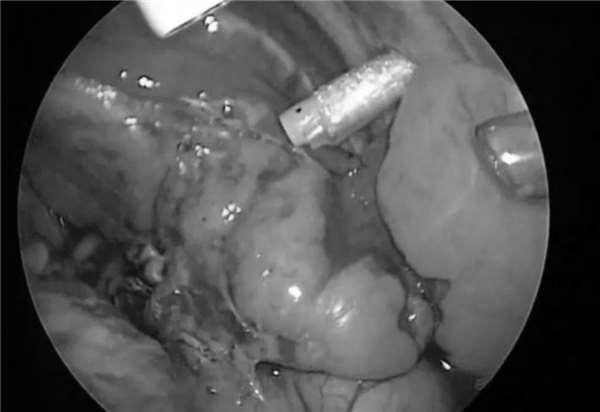

之後,山高開啟了自己不斷挑戰自我的職業生涯,他成為日本實施內視鏡手術最多的外科醫生,包括在阻塞的膽管上進行的手術。

這個嬰兒,腸子比正常位置低了很多,手術需要極高的精準度,手術難度非常大,嬰兒體型太小,他只能切開一個兩公分的小口。

任何稍微用力的觸碰,都有可能撕裂嬰兒細小的組織。

「這一塊,只能用70%左右的力道。」

手術中,山高不停在重複的一個詞是:「輕點,輕點!」

到了第二天,真正的戰鬥打響了,一開始進行得很順利,開口,插管。

儘管在手術前,山高設想了每一個可能發生的意外情況,但是,他最擔心的事還是發生了,波琦的右肺下半葉組織沾黏在一起,擋住了動脈和靜脈。

憑著一萬台手術積累的經驗和勇氣,他沉住氣,不斷提醒手術室的人,也包括他自己:「不要慌,慢慢來...」,器具在波琦的肺泡叢林中艱難游弋,一遍遍反覆觀察、尋找,終於他們找到了那根藏起來的肺動脈。

山高把動脈結紮,然後小心地剪斷了它。

接下來,山高開始尋找靜脈,過了很久,他又在黏合在一起的肺葉深處發現了一條4公分長的靜脈。